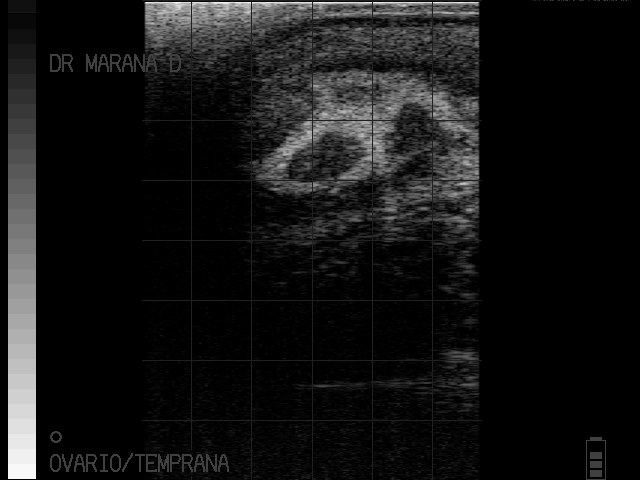

Metritis

Piometra severa

imagenes cortesia:

MVZ MsC David Maraña Peña Especialista en Reproducción Bovina